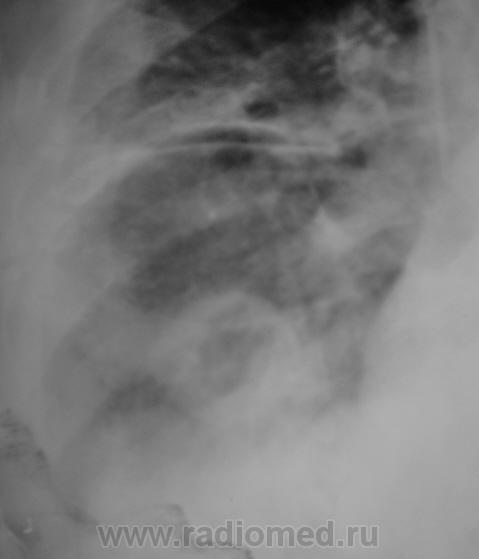

У пациента КТ не на диске, а распечатка. Вот и представляю так. как перефотографировал. Какое мнение будет уважаемые коллеги?

Валентин Львович! Мне думается, что распечатка КТ на бумаге сама по себе уже не информативна и не предназначена для диагностики. Смысла ее перефотографировать абсолютно не имеется.

Но все таки абсцедирующая пневмония!

ИМХО: впечатление о значительной положительной динамике создаётся, на мой взгляд, по причине уменьшения объёма выпота в плевральной полости,вероятно потому, что в последней стоит катетер.Тень абсцесса хоть и стала меньше, но имеет ещё большие размеры.По КТ абсцесс виден и в нижнем поле левого лёгкого; картина самих абсцессов, их множественность, быстрое развитие( через 3 дня после оперативного вмешательства), вызывает подозрение на эмболию легочной артерии( о чём уже говорили коллеги из области).

согласен с ТЭЛА. На КТ подобное видел - субплеврально, полость деструкции с бронхо-сосудистым тяжем к корню легкого, жидкость в плевр полости, быстрая динамика...

Было бы похоже на инфаркт-пневмонию (за счёт тромбоэмболии мелких ветвеё ЛА) если бы не КТ ОГК (массивная полисегментарная инфильтрация и не одна полость).